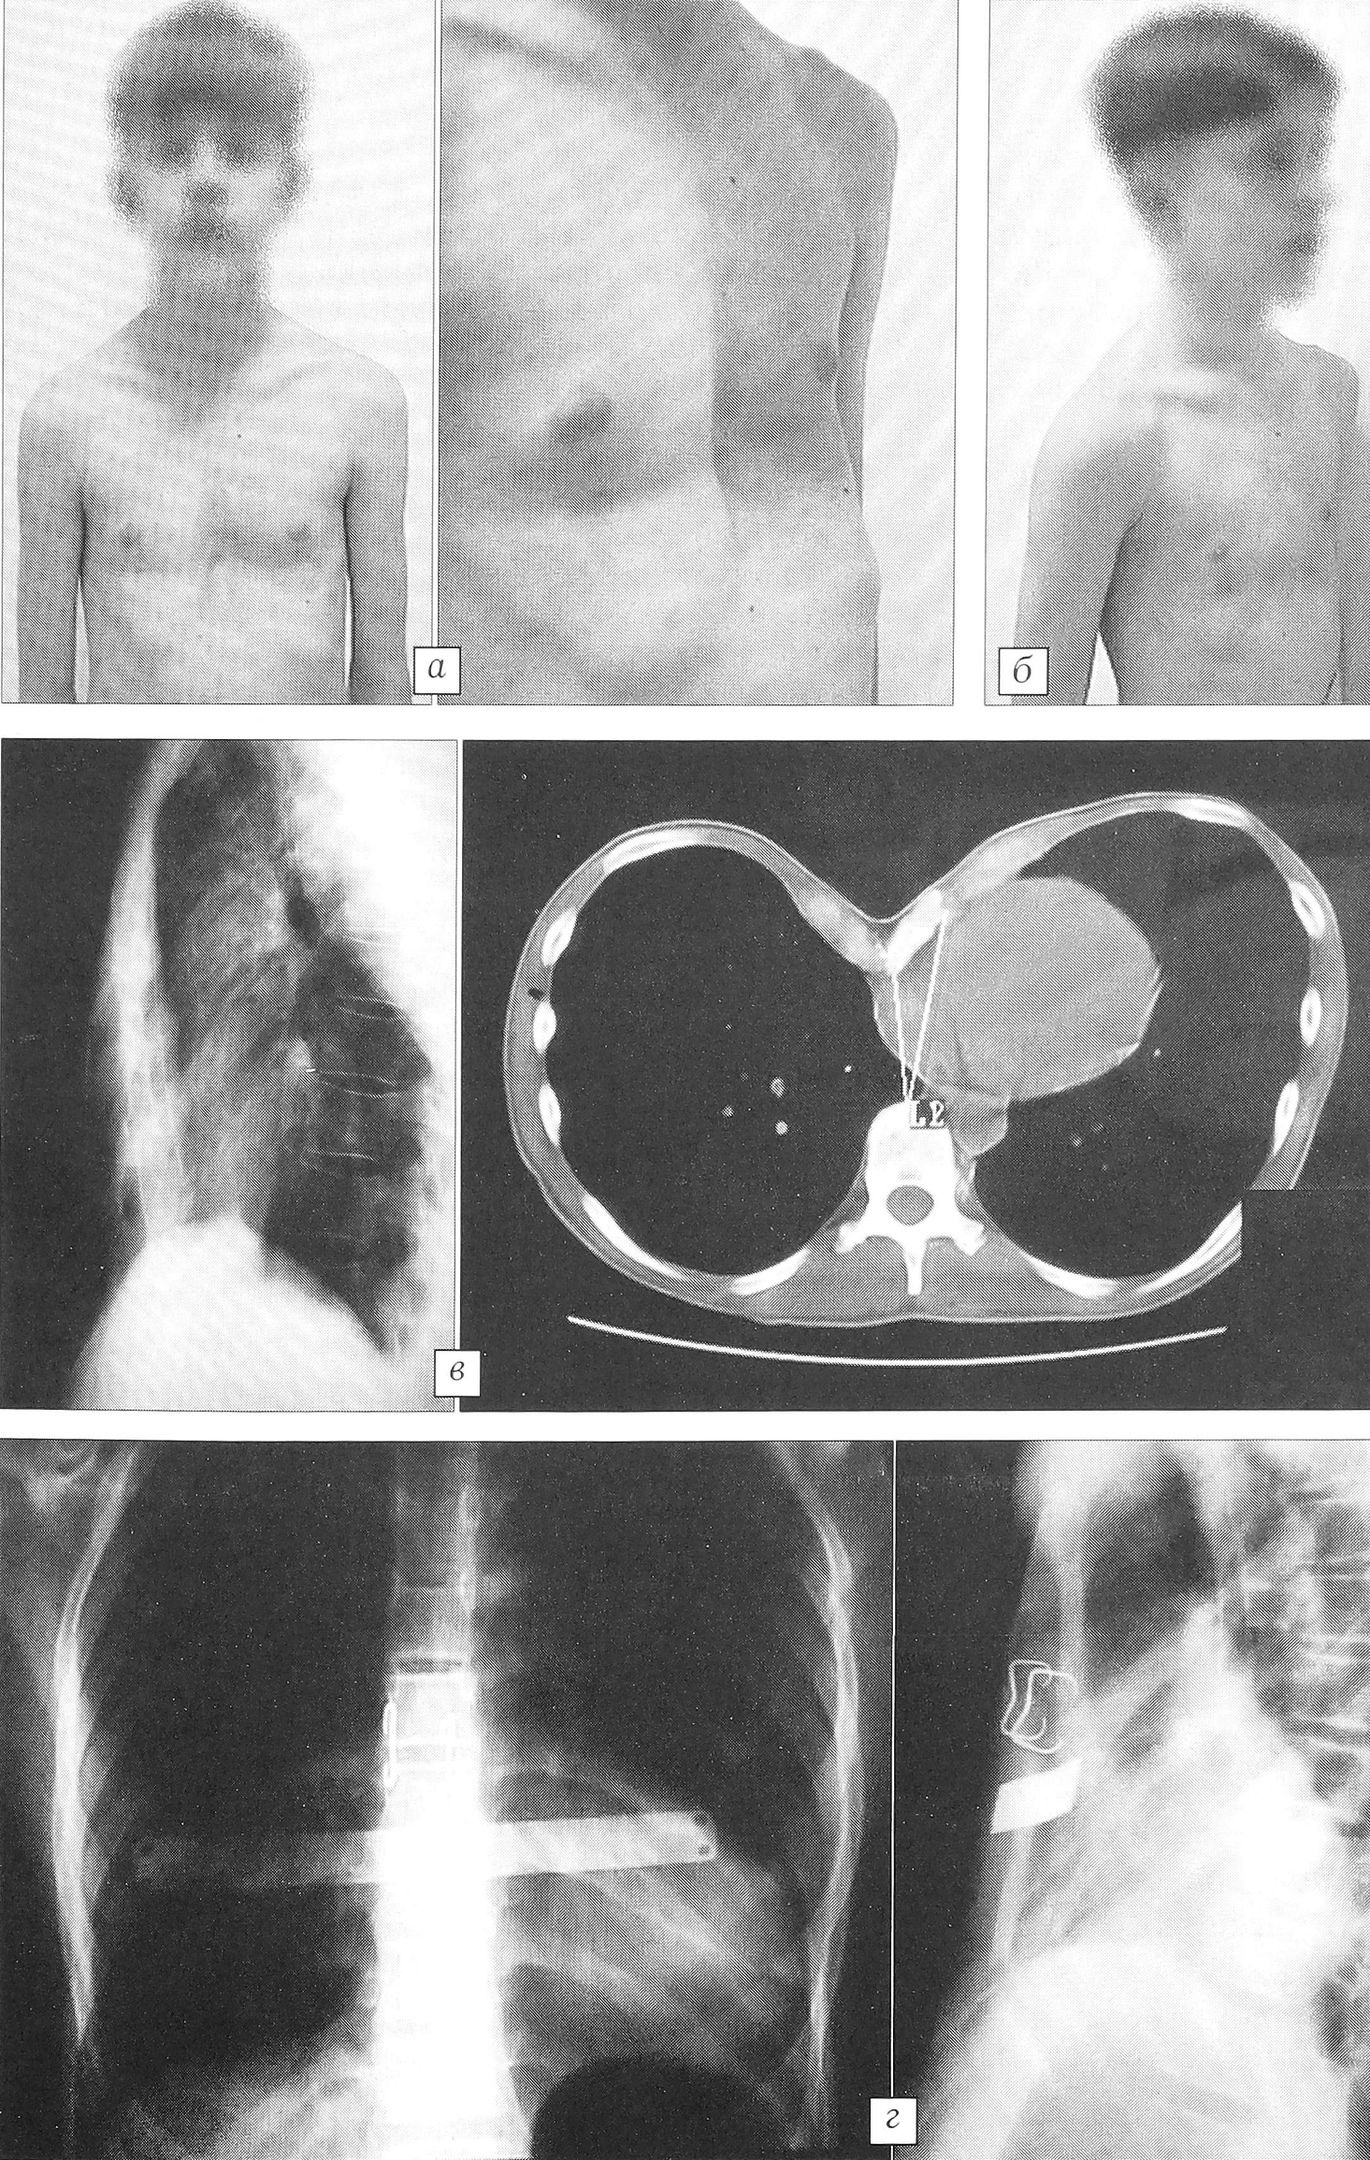

Пример 3. Больной П., 16 лет, диагноз: воронкообразная деформация грудной клетки III степени. При поступлении жалобы на одышку после незначительной физической нагрузки, периодические боли за грудиной. На ЭКГ отмечается перегрузка правых отделов сердца, блокада правой ножки пучка Гисса, при исследовании функции внешнего дыхания — снижение функциональной остаточной емкости легких на 30%. Произведена торакопластика по модифицированной методике Salamaa—Paltia. В послеоперационном периоде проводилось активное дренирование правой плевральной полости в течение 2 сут. Получено 450 мл геморрагического отделяемого. Дальнейшее течение послеоперационного периода без осложнений. Через 6 мес удалена пластина Paltia. Результат лечения хороший, каркас грудной клетки сформирован правильно. При осмотре через 2 года: каркас грудной клетки сформирован правильно, на фоне роста (пациент вырос на 15 см) рецидива деформации нет (рис. 3).

Рис. 3. Больной П. 16 лет. Воронкообразная деформация грудной клетки III степени, асимметричный корпорокостальный тип.a — внешний вид до операции, б — через 2 года после торакопластики по модифицированной методике Salamaa—Paltia; в — рентгенограмма и компьютерная томограмма грудной клетки до операции, г — рентгенограммы после торакопластики.